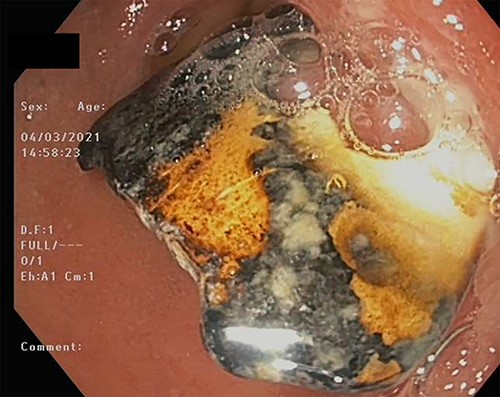

Patient RB a 68-year-old gentleman presented to the emergency department with epigastric pain, melaena and coffee ground vomitus. His medical history is significant for ischaemic heart disease, Type 2 diabetes mellitus, Parkinson’s disease and a previous open appendicectomy His initial haemoglobin was 85 g/L, urea was 18 mmol/L. The patient was resuscitated and was given 2 units of packed red blood cells and high dose 80 mg of IV pantoprazole. An urgent upper gastrointestinal endoscopy revealed an entrenched FB at the duodenal bulb measuring 20 mm. A snare and a large biopsy forceps were unable to retrieve the object. Further attempts were abandoned due to the surrounding ulceration and fears of an impending perforation, without being able to identify the FB as it had a metallic appearance.

On Day 7, a repeat upper gastrointestinal endoscopy was performed. The FB remained in the first part of the duodenum which it had begun to erode through posteriorly (Fig. 7). The endoscopy was fitted with an overtube and with the help of a snare the embedded FB was successfully retrieved.